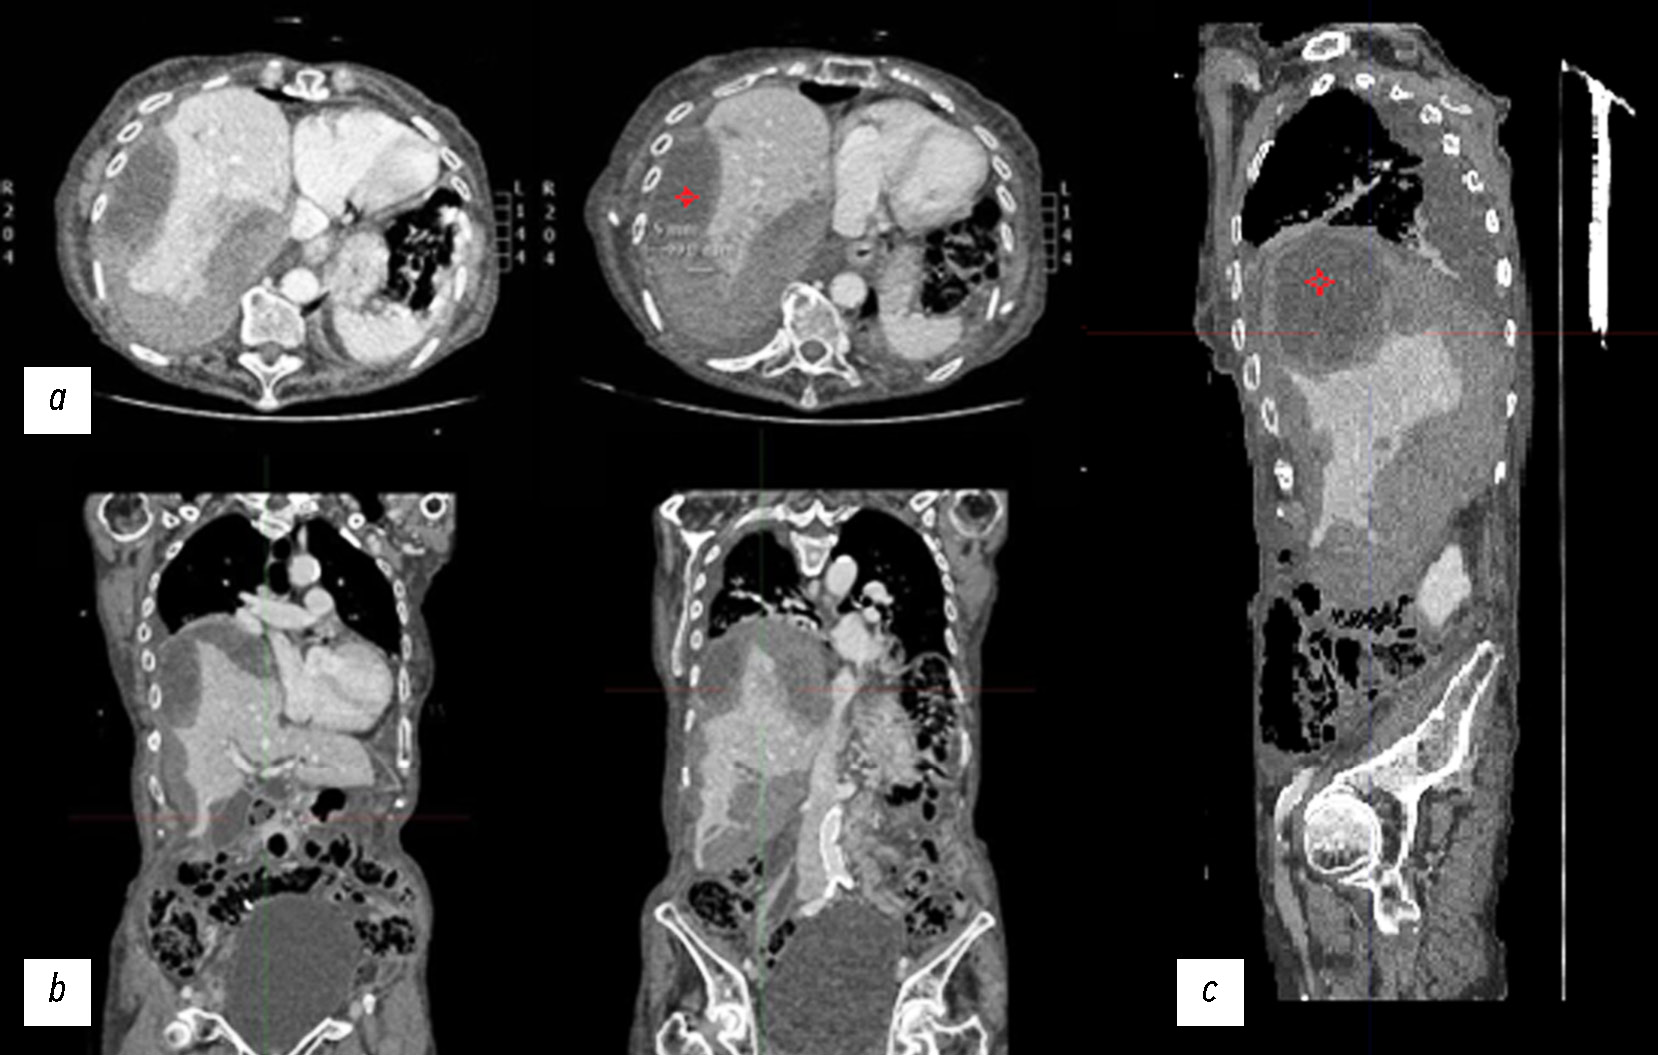

Через несколько дней была проведена повторная КТ с контрастным усилением, по результатам которой выявили разрыв паренхимы печени в VII сегменте на уровне ворот печени. Повреждение сопровождалось обширной интракапсулярной гиподенсной сферической зоной, интрапаренхиматозной гематомой толщиной до 5 см и диффузной субкапсулярной гематомой, занимающей 40–50% площади поверхности (II–III степени по шкале повреждений печени Американской ассоциации хирургии травм [The American Association for the Surgery of Trauma, AAST]). На КТ-снимках выявили умеренный объём гемоперитонеума, вероятно, из печени (рис. 2).

Рис. 2. Снимки компьютерной томографии с контрастным усилением в портально-венозной фазе: a — аксиальная плоскость; b — корональная плоскость; c — сагиттальная плоскость.

На снимках в аксиальной, корональной и сагиттальной плоскостях по сравнению с предыдущими снимками выявили усугубление разрыва паренхимы печени в VII сегменте на уровне ворот печени с обширной распространённой интракапсулярной гематомой сферической формы с максимальной толщиной около 5 см (обозначена красной звёздочкой) и субкапсулярной гематомой. Кроме того, наблюдалось растяжение мочевого пузыря.